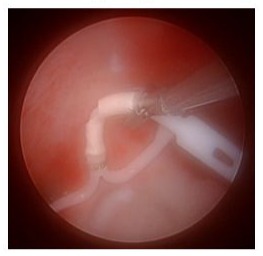

We began the procedure with a hysteroscopic approach. The hysteroscope was inserted through the cervix and guided into the uterine cavity. Upon inspection, the Mirena IUD was not visible.

Figure 2: Hysteroscopic global survey showing inability to visualize the Mirena IUD.